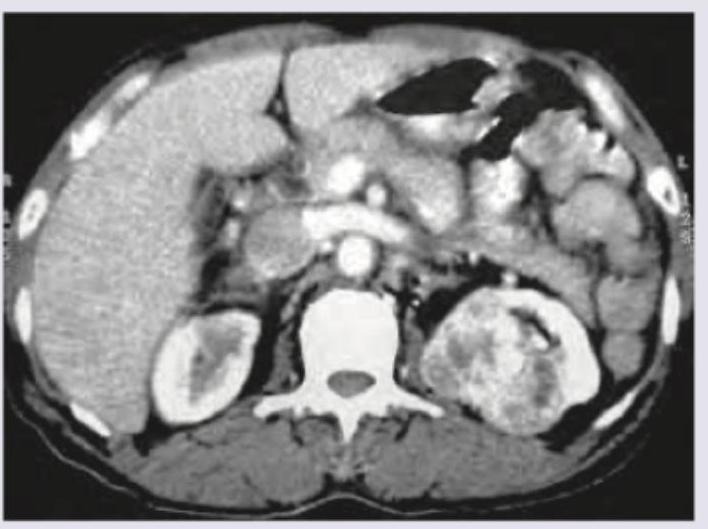

A 50-year-old man went for his annual medical check-up. CT scan is shown below. Diagnosis is?

Question 5: A 50-year-old man went for his annual medical check-up. CT scan is shown below. Diagnosis is?

- A. Renal cell carcinoma

- B. Renal angiomyolipoma (Correct Answer)

- C. Renal cyst

- D. Rhabdomyosarcoma

Explanation: ***Renal angiomyolipoma*** - The CT scan shows a renal mass with areas of **macroscopic fat density**, which is the hallmark of an angiomyolipoma. - Angiomyolipomas are **benign renal tumors** composed of variable amounts of smooth muscle, vascular tissue, and mature adipose tissue. *Renal cell carcinoma* - While renal cell carcinoma can present as a solid renal mass, it typically does **not contain macroscopic fat**. - It usually enhances heterogeneously with contrast and may show areas of necrosis or hemorrhage, but the presence of fat rules out typical RCC. *Renal cyst* - Renal cysts are typically **simple fluid-filled structures** with very low attenuation values (close to water) and **do not contain solid components or fat**. - They also have thin, imperceptible walls and do not enhance with contrast. *Rhabdomyosarcoma* - Rhabdomyosarcomas are **malignant soft tissue tumors** rarely found in the kidney, and would appear as a solid, often heterogeneous mass on CT. - They do **not contain fat** and are aggressive tumors, often associated with a different patient demographic (e.g., children).